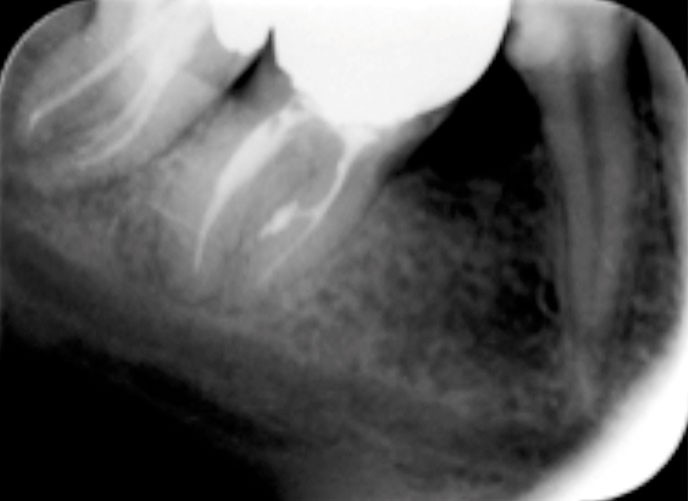

Anatomiquement parlant, les voies de communications entre l’endodonte et le parodonte seront constituées par des canaux radiculaires, qu’ils soient principaux, latéraux, secondaires ou accessoires. Un canal latéral est une ramification du canal principal située dans la région médiane ou coronaire le reliant au ligament alvéolo-dentaire, alors que le canal secondaire est situé dans la région apicale. Le canal accessoire est une ramification du canal secondaire (fig. 1).

Les fêlures et fractures ou les perforations dentaires sont d’autres voies possibles de contamination. Le premier tissu parodontal atteint au contact de la racine sera le desmodonte. La diffusion de l’infection suivra la voie du sulcus gingival ou celle osseuse alvéolaire.

Lorsqu’un patient se présente en consultation avec une lésion au contact d’une dent (fig. 2), le praticien doit suivre une démarche diagnostique afin de recueillir le maximum d’informations sur la situation clinique :